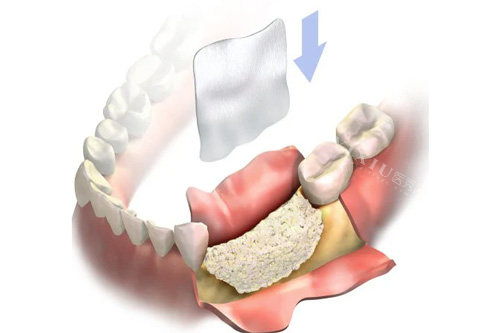

"我牙槽骨薄得像煎饼,其他医院都说得先植骨等半年。"58岁的张大爷摸着刚装好的全口种植牙说,"韩医生直接用了穿颧种植技术,上午种完下午就能啃排骨!"这种看似"冒险"的操作背后,是15年累计3000+例手术的经验支撑。

"988元起套餐主要针对单颗后牙缺失,且牙槽骨条件良好的患者。"前台护士指着价目表解释,"如果需要骨增量手术或者选择高端品牌,价格会相应上浮。"这种透明的分级定价,让患者刘先生感慨:"至少知道钱花在哪了,不像有些地方含糊其辞。"